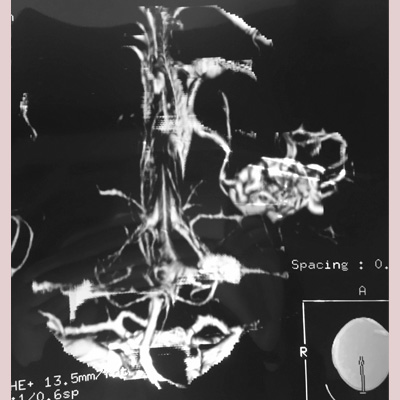

Brain Arteriovenous Malformations (AVM), as well as other Vascular Malformations are resected with sophisticated Microsurgical techniques in appropriately selected cases, or referred for Endovascular Embolization, Stereotactic Radiosurgery (SRS), or a combination of these treatment modalities with high success rates and safety and efficacy.